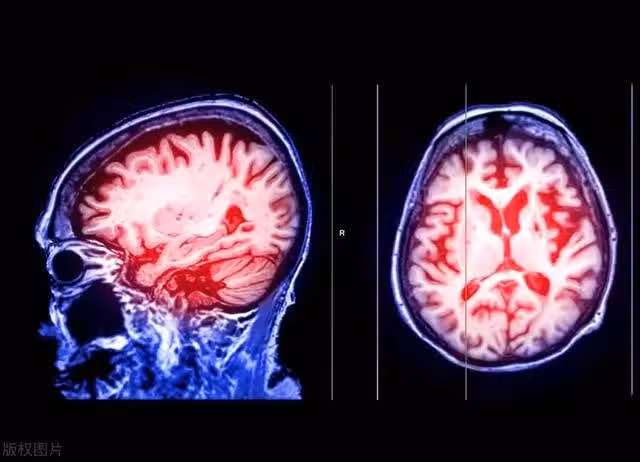

腦血管病是一種常見且具有嚴重後果的疾病,它包括腦梗塞和腦出血兩種主要類型。在這些疾病發生之前,往往會有一段時間的預警期,被稱為「止損期」。這個止損期是識別並干預潛在腦血管風險的黃金機會,因為錯過了這個時機,可能會導致不可逆轉的腦損傷。

腦血管病是指腦血管的功能異常引起的疾病,包括腦梗塞和腦出血。這些疾病的主要風險因素包括高血壓、高血脂、糖尿病、吸菸、肥胖以及家族遺傳等。這些因素會導致動脈硬化、血栓形成和血管破裂,從而引發腦血管病。